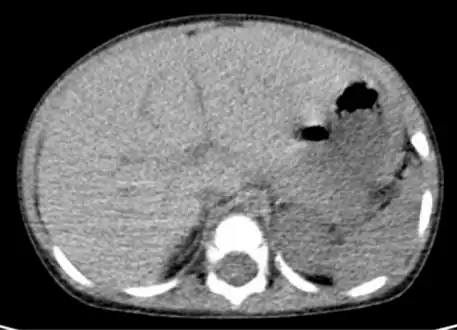

-

Computed tomography finding of hepatomegaly. -

On abdominal ultrasonography, the liver can be measured by the maximum dimension on a sagittal plane view through the midclavicular line, which is normally up to 18 cm in adults.[2] It is also possible to measure the cranio-caudal dimension, which is normally up to 15 cm in adults.[2] This can be measured together with the ventro-dorsal dimension (or depth), which is normally up to 13 cm.[2] Also, the caudate lobe is enlarged in many diseases. In the axial plane, the caudate lobe should normally have a cross-section of less than 0.55 of the rest of the liver.[2]

Other ultrasound studies have suggested hepatomegaly as being defined as a longitudinal axis > 15.5 cm at the hepatic midline, or > 16.0 cm at the midclavicular line.[16][17]

Computerized tomography (CT) can help to obtain accurate anatomical information, in individuals with hepatomegaly for the purpose of a complete diagnosis.[21]